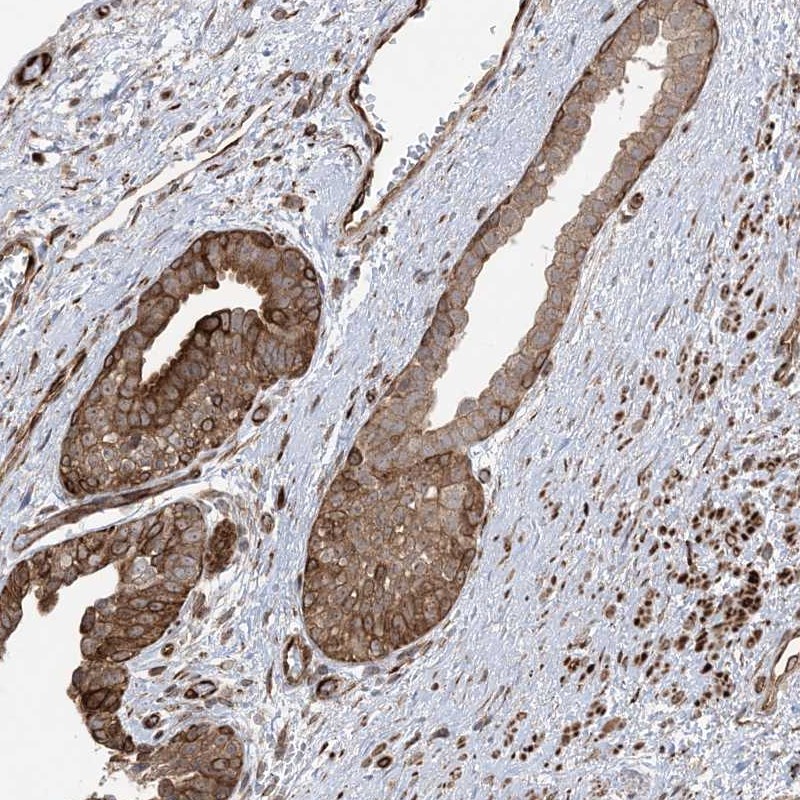

Immunohistochemical staining of human prostate shows distinct cytoplasmic, membranous and nuclear positivity in glandular cells.